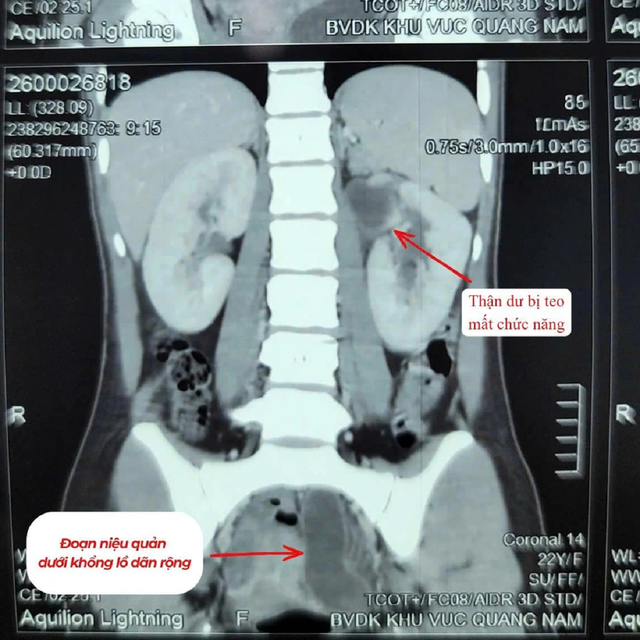

Người bệnh nhập viện trong tình trạng sốt cao, đau vùng hông trái. Qua thăm khám lâm sàng và thực hiện các xét nghiệm cận lâm sàng, các bác sĩ chẩn đoán bệnh nhân mắc dị tật thận - niệu quản đôi bên trái (tổng 3 thận). Trong đó, một thận đã mất chức năng, niệu quản giãn lớn bất thường, chứa nhiều mủ gây nhiễm trùng nặng.

Hình ảnh thận trên phim. Ảnh: BVCC.

Qua thăm khám và thực hiện các cận lâm sàng cần thiết, bác sĩ chẩn đoán bệnh nhân có 2 quả thận bên trái, trong đó một thận bị mất chức năng. Niệu quản đi từ thận mất chức năng giãn to bất thường, chứa đầy mủ gây nhiễm trùng nặng.